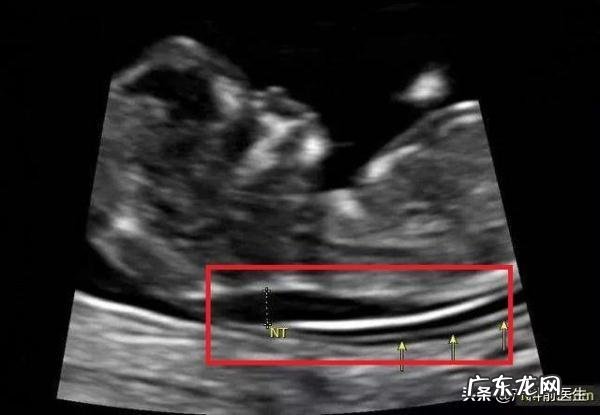

孕妇做NT值为2.6 , 属不属于高风险 , 没做无创 , 只做了早期糖筛低风险?对于宝妈们来讲 , NT并不是特别陌生 , 大部分宝妈知道要做孕11-13+6周时需要做NT了解胎儿是否存在异常 , 主要的筛查非整倍体异常或胎儿心脏异常 。研究提示NT值增加 , 那么胎儿存在非整倍体异常和胎儿心脏的异常的概率增加 。

NT是做B超的 , B超单上主要的数据包括是否有误鼻骨 , NT多少 , CRL多少 。缺一不可 。NT值跟CRL是有关联性的 。

题主NT值2.6mm,但是没有给出CRL值 , 故不好说 , 而且对于我来讲 , 我更看重NT值大于

3mm的意义 。加上早唐筛查提示低风险 , 个人觉得问题不大 , 继续观察 , 按时产检就行 , 如果不放心 , 那么建议做个无创DNA检查 。